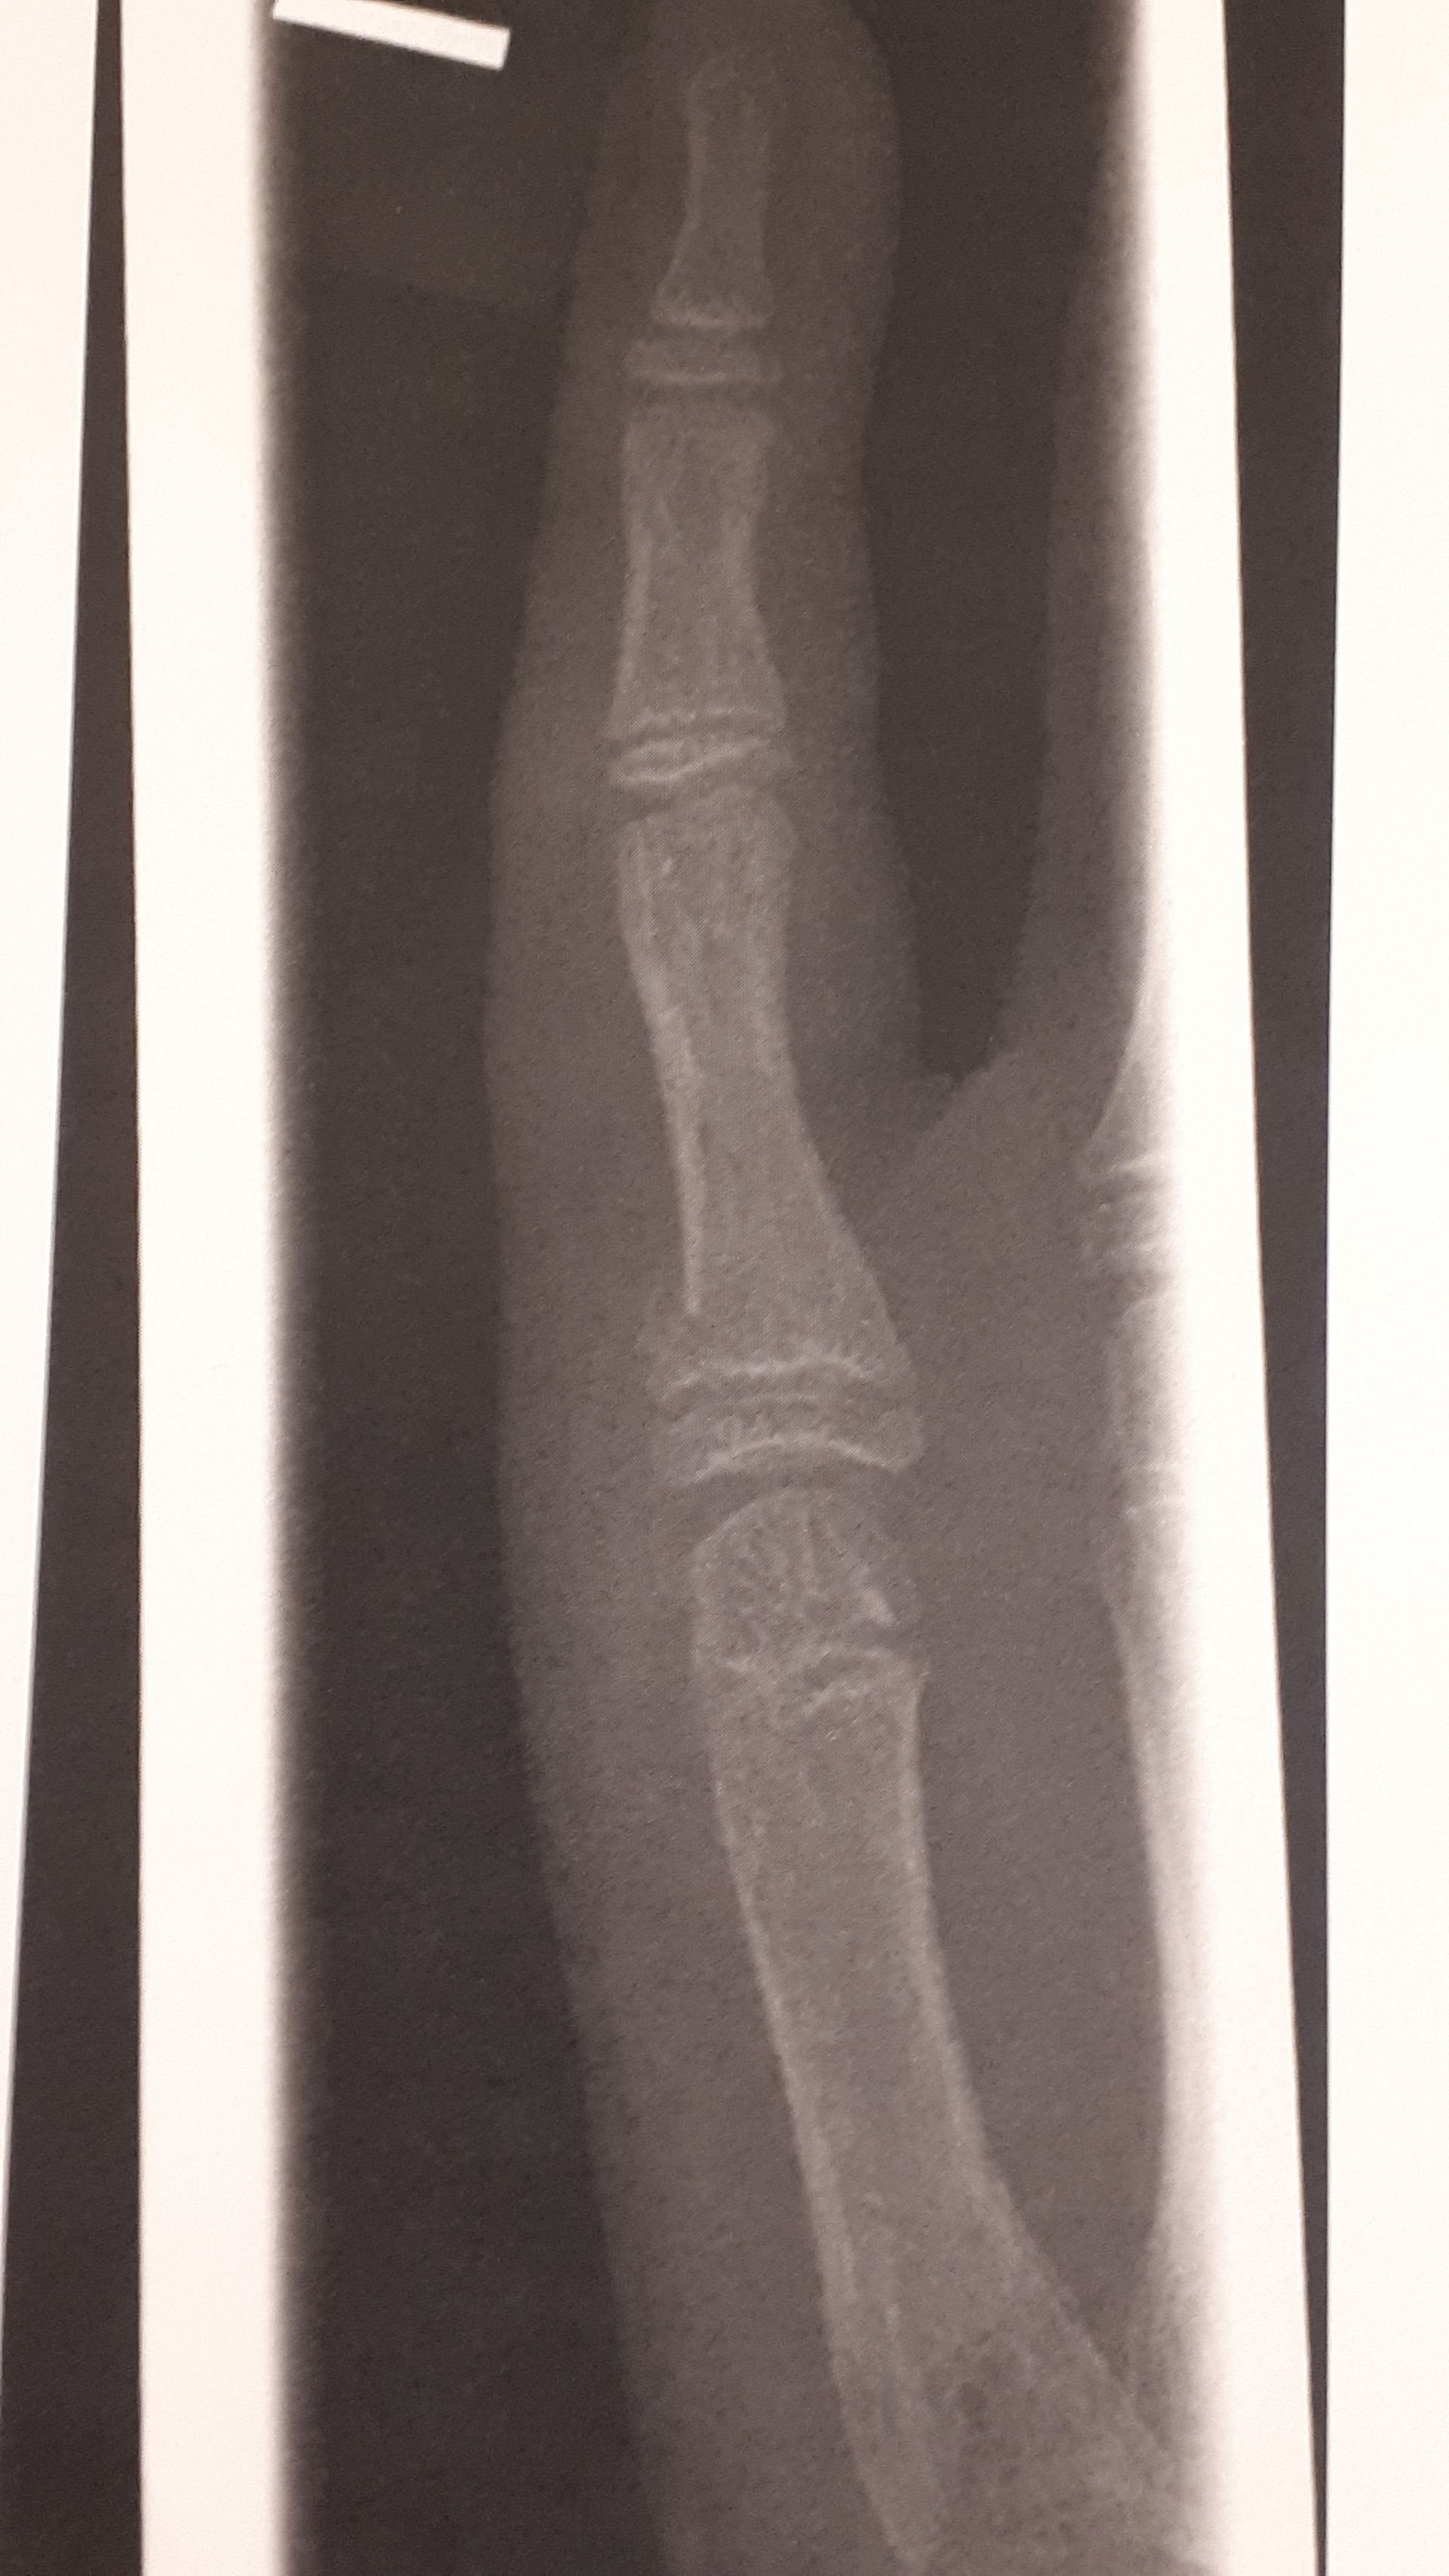

CactusCat14108 #gegenDatenschutz-Mannvor 3 MonatenAnonyman welcher Stelle genau?Ich schick gleich bearbeitetes bild mit rotem kreis

Anonymvor 3 MonatenCactusCat14108 #gegenDatenschutz-MannIch schick gleich bearbeitetes bild mit rotem kreisDanke

CactusCat14108 #gegenDatenschutz-Mannvor 3 MonatenKatze®️Am kleinen Finger OP haben die bei mir nd gemacht, lohnt nd sagten sieBei mir isser verdreht, und muss mit so 2 kleinen drähten befestigt werden

Anonymvor 3 MonatenCactusCat14108 #gegenDatenschutz-MannBildkomisch dass man es auf dem bild nicht erkennt, aber der arzt hat es erkannt

Anonymvor 3 MonatenAnonymkomisch dass man es auf dem bild nicht erkennt, aber der arzt hat es erkanntalso dass es gebrochen ist

Ich schick gleich bearbeitetes bild mit rotem kreis

Ist verdreht

Bei mir isser verdreht, und muss mit so 2 kleinen drähten befestigt werden

Und die drähte kommen unter die haut halt

komisch dass man es auf dem bild nicht erkennt, aber der arzt hat es erkannt

also dass es gebrochen ist